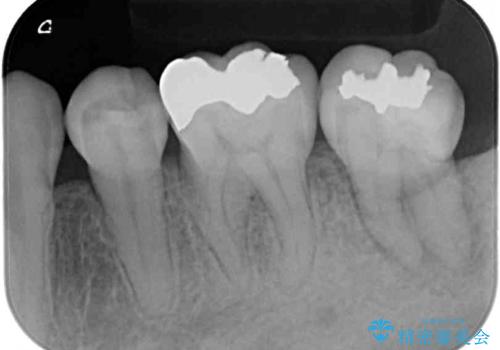

- 左下の奥歯に違和感を感じて来院された患者様です。

診察をした結果、歯根にまで及んだ虫歯と歯周病による著しい骨欠損が認められ、抜歯をせざるを得ない状況でした。